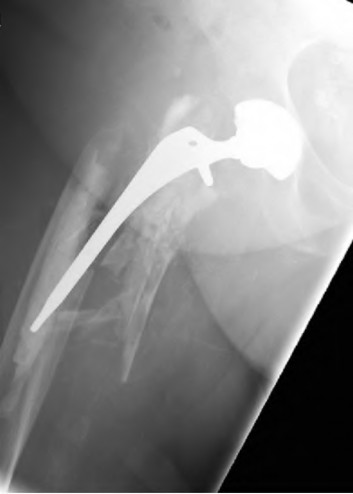

The radiograph demonstrates a periprosthetic femur fracture extending to the tip of the stem. The long spiral fracture is consistent with a loose implant. The bone stock is sufficient. Therefore, this fracture pattern would classify as a B2 using the Vancouver classification system. The Vancouver classification for periprosthetic femoral fractures is simple yet incorporates all the pertinent factors such a location, stem fixation, and bone stock. Type A is a trochanteric fracture- lesser or greater. These can be treated non-operatively usually and ORIF if symptomatic. Type B fractures are around or just below the stem and are subdivided into three types. Type B1 is a fracture with a well fixed stem.

The treatment is cable plating or allograft struts or a combination of the two. Type B2 is a fracture with a loose stem with good bone stock. The treatment is a cementless porous coated long stem atleast two diameter length past the

fracture site. Type B3 is a fracture with a loose stem and comminution. For younger patients, use cementless porous coated long stems with allograft struts. For older patients, consider a tumor prosthesis. Cement fixation is sometimes necessary Type C is a fracture well below the stem tip. These can be treated independently of the prosthesis.

Springer et al showed optimal outcomes with revision involving long extensively-coated femoral stems for Vancouver B fractures.

Masri et al review the classification and treatment of periprosthetic femur fractures.